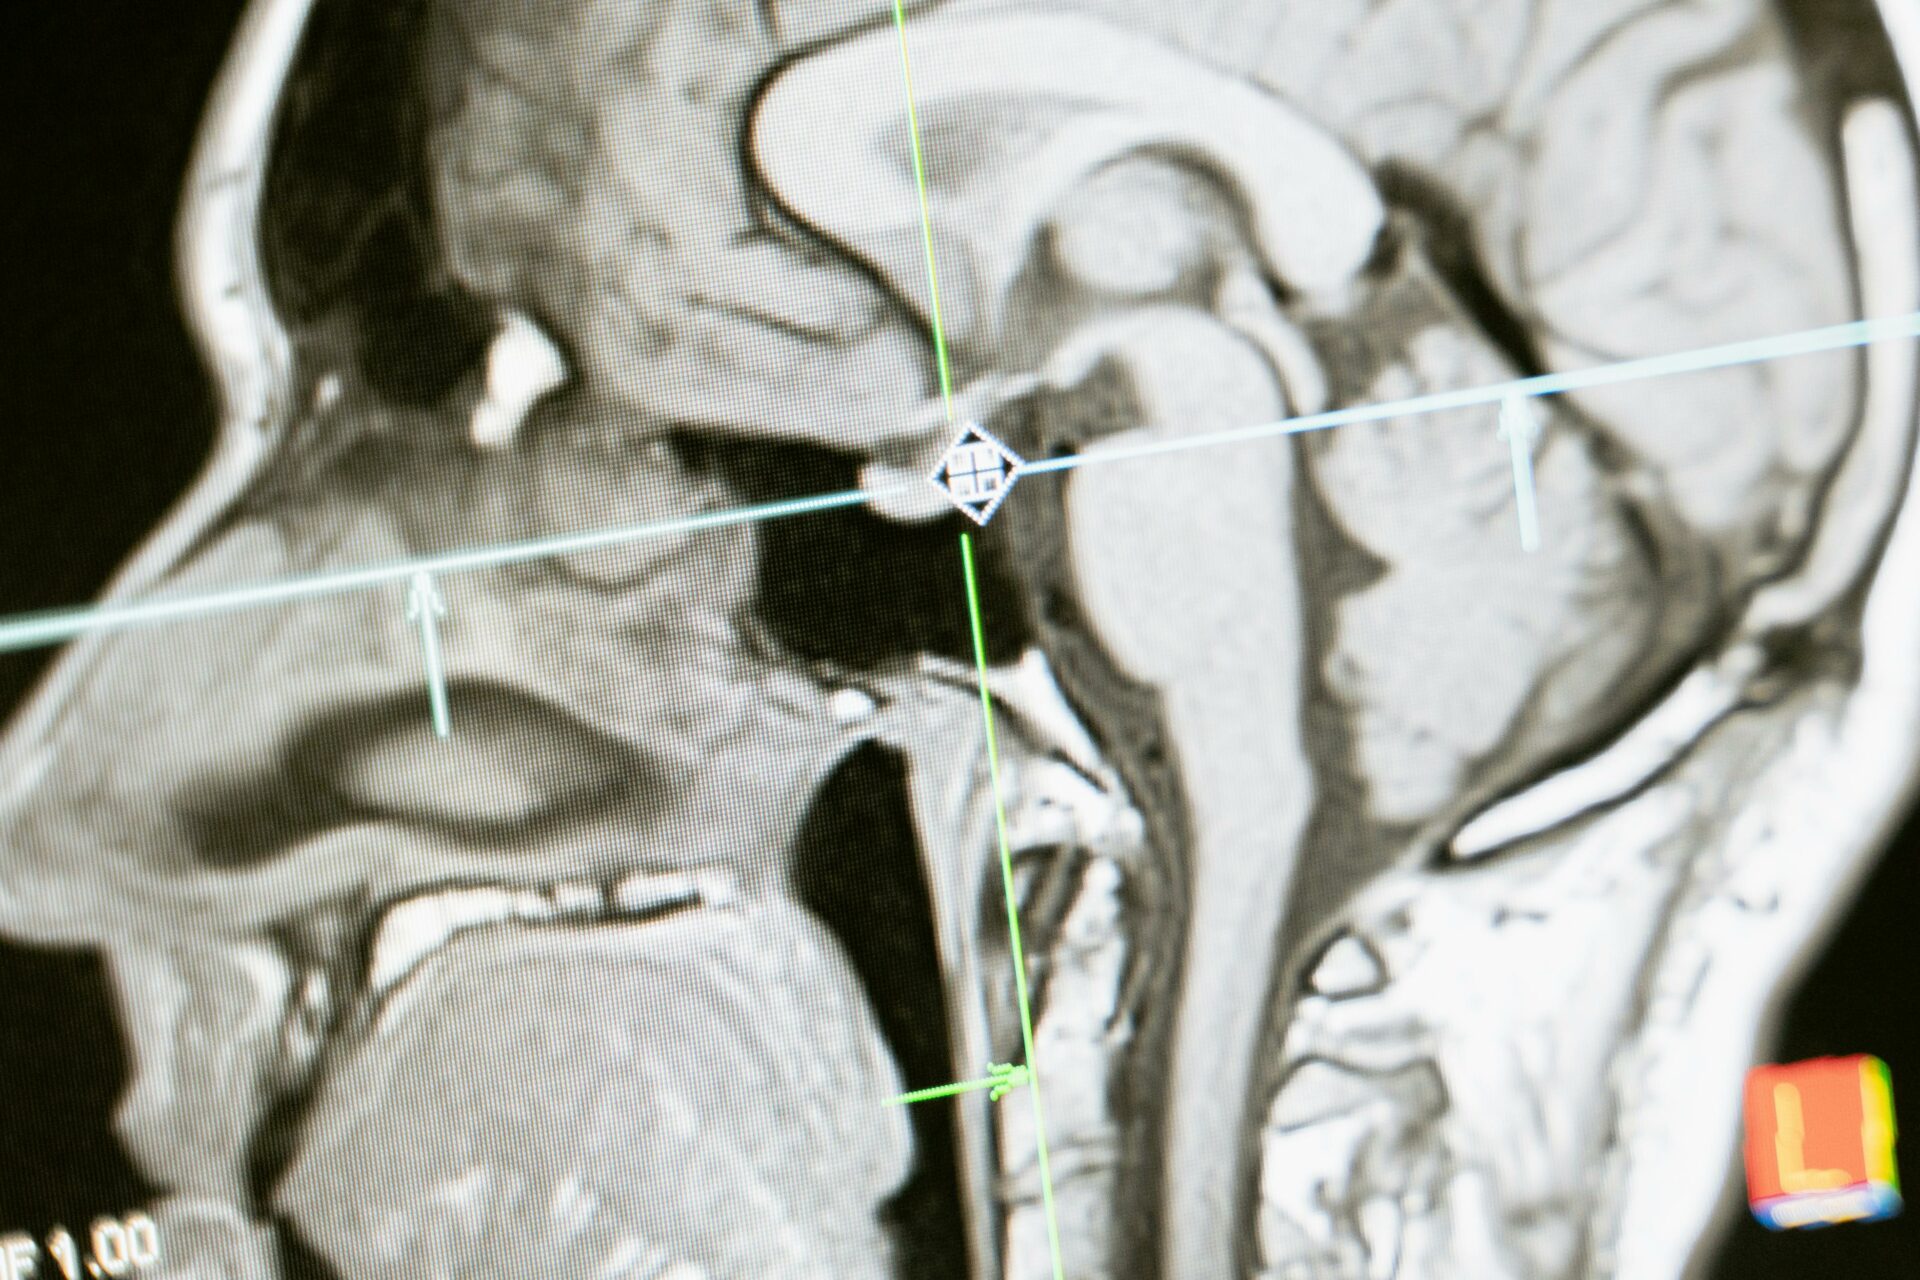

Тимот анализирал MRI-снимки од 26 астронаути и ги споредил со контролна група од 24 лица кои учествувале во т.н. студија на мирување во кревет со наведната глава надолу. Испитаниците во контролната група лежеле до 60 дена со главата под нивото на нозете, со цел да се симулира дел од ефектите на микрогравитацијата.

Резултатите покажале дека мозокот кај астронаутите се поместува значително повеќе отколку кај контролната група, а интензитетот на промените бил директно поврзан со должината на престојот во вселената.